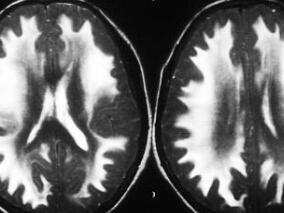

1小时条评论男,73岁,右利手。 主诉:因右侧肢体不自主活动6天入院。 病史:患者于9天前晨起时无明显诱因下出现右侧肢体不自主活动,表现不自主快速、无目的、无节律、粗大舞蹈样动作,意志不能控制。无不自主眨眼、噘嘴、吞吐舌等动作,言语清晰,进食及饮水正常,无肢体无...